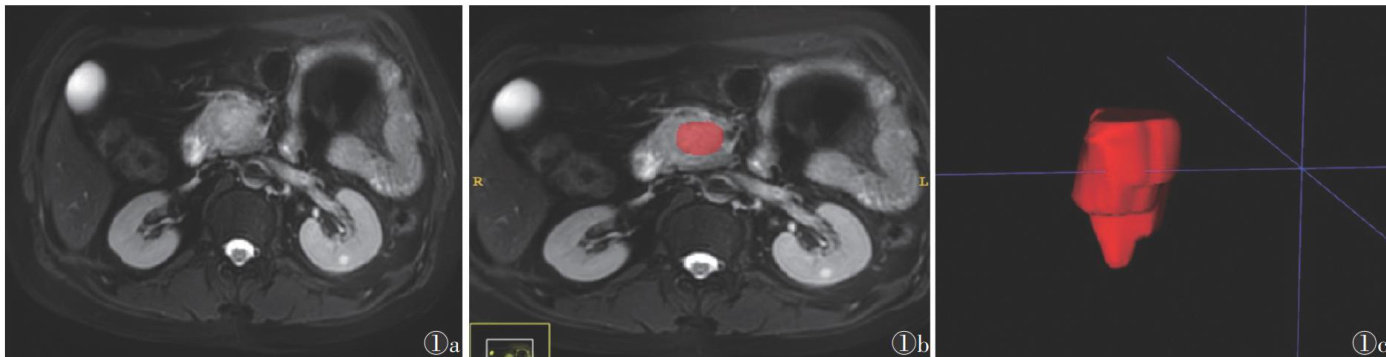

[Abstract]Objective:ToexplorethepreoperativevalueofMRIradiomicsmodelforthepathologicaldiferentiationdegree of pancreaticductaladenocarcinoma(PDAC).Methods:ThepancreaticMRIimagesandclinicaldataof96PDACpatients wereretrospectivelycollected.Thepatientsweredividedintoamedium-highdiferentiationgroup(52cases)andalow diferentitiongroup(44cases)basedonthepathologicaldiferentiationdegreeaftersurgeryROIsweredelineatedforthe tumorlayerbylayer,fromtheTSPIR,DWI,arterial phase,parenchymal phaseandvenousphaseiamges.Theradiomics featureswere extractedusingtheopen-sourcesoftware,andaradiomicsmodelwasestablishedusingsupport vector machine(SVM)asaclassifier.96patientswererandomlydividedintoatrainingcohort(67cases)andatesting cohort(29cases)ataratioof7:3.Thenthefive-foldcros-validationwasusedtointerallyvalidatetheradiomicsmodel andidentifythebesthyperparametersinthetrainingcohort.ROCcurveswereusedtoevaluatetheeficacyofthemodel. Results:TheclinicaldataorMRIfeatureshadnosignificantdiferences betweenthemedium-highdiferentiationandlow differentiation groups(all P >0.05).A radiomicsmodel named Mean-RFE-18-SVM,capable of distinguishing the pathological diferentiationdegreeofPDAC,wasestablishedusing18radiomicsfeaturesselectedfromfivesequenceimages.Themodel performedwellininternalvalidation,withanaverageAUCofO.829,andtheAUCsforthetrainingandtestingcohorts were0.933(95%CI0.874-0.991)and0.846(95%CI0.697-0.995),respectively,withtheacuraciesof0.881and0.828,the sensivitiesof10oOand0.875,thespecificitiesof0.742and0.769,respectivelyConclusions:Themodelestablishedbased onMRIradiomicsfeaturesdemonstratesgooddiagnosticeficacyinnon-invasivepreoperativepredictionofthepathological diferentiationdegreeofPDAC.Itcanprovidemoredecisionsupportinformationforpersonalizeddiagnosisandtreatmentas well as prognosis assessment of PDAC patients.

胰腺导管腺癌(pancreatic ductal adenocarcinoma,PDAC)恶性程度高,预后差,5年生存率仅 10%[1-2] PDAC的病理分化程度是评估患者预后的重要指标,可指导临床制订治疗方案[3-4]。(剩余7442字)